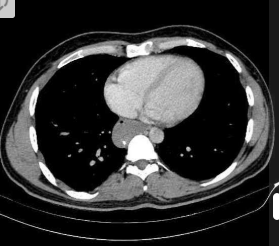

RN a termo.

Cardiomegalia massiva em um neonato com pulmão normal (sem edema alveolar ou intersticial, sem derrame pleural)

Cardiomiopatia neonatal.